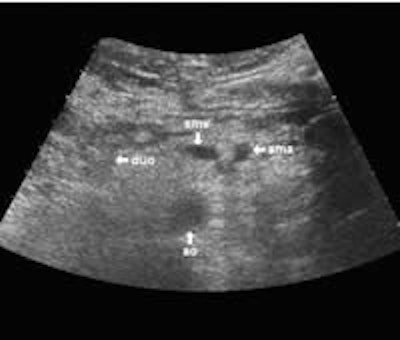

The following study describes anatomical landmarks in the ordinary pancreas of a thin patient:

Transverse planes in caudal direction:

The dorsal aspect of the head takes the shape of a hook surrounding the right side of the superior mesenteric vein; the sharp left-pointing tip of the hook behind the vein constitutes the uncinate process. The splenic vein runs from the left along the dorsal border of the tail and body to the superior mesenteric vein, where these veins join to form the portal vein behind the "neck" of the pancreas. The portal vein then leaves the pancreas to the right and slightly upwards and runs into the liver hilum.

The main bile duct runs from the liver hilum to the right of and above the portal vein into the right dorsal part of the pancreatic head, where it runs vertically into the duodenum. The pancreatic duct typically runs along the body and tail to join the common bile duct near the duodenum. The gastroduodenal artery is sometimes seen in its position along the front margin of the pancreatic head, where it runs in a nearly parallel direction to the common bile duct. Like the common bile duct and pancreatic duct, however, the gastroduodenal artery is not always clearly seen due to its small diameter. The duodenum covers the right and bottom margins of the pancreatic head.